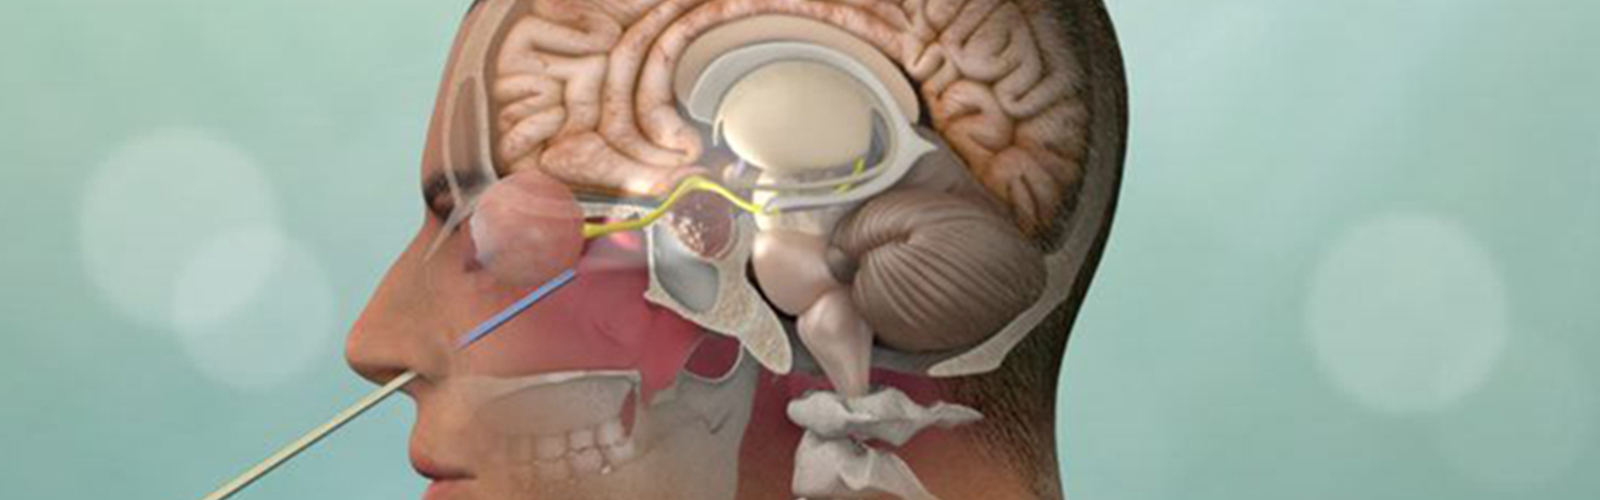

Neurocirugía

Soy neurocirujano egresado del

Cuento con un

en uno de los más reconocidos programas de tumores cerebrales, base de cráneo y Neuro-Oncología -

- Estoy altamente entrenado para realizar abordajes de mínima invasión en cráneo y columna.